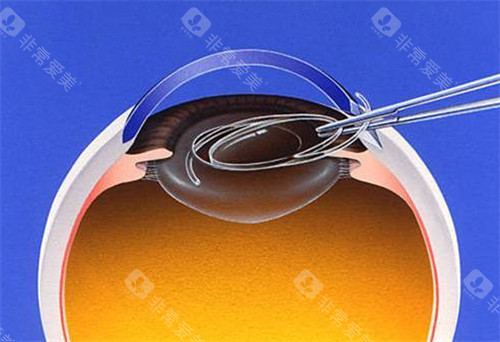

白内障正规开展了多种白内障手术,包括超声乳化白内障吸除术等,手术技术成熟,术后结果良好。

此外,科室还开展了一些潮流的眼科手术技术,如飞秒激光辅助白内障手术等,大大提高了手术的可靠性和有效性。